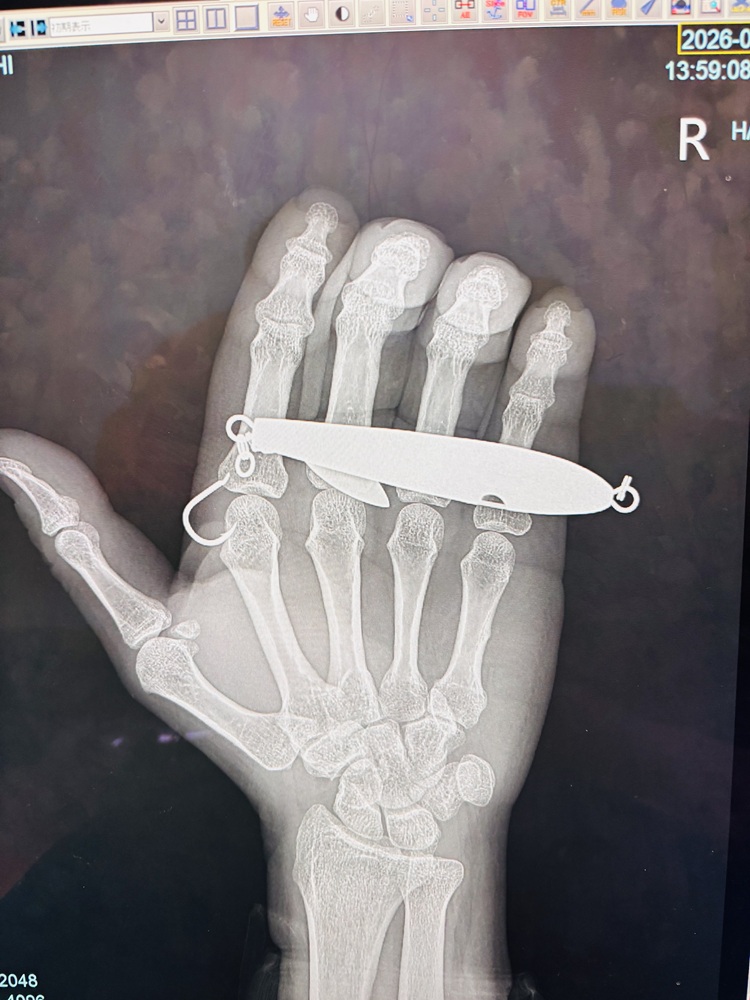

とりあえずフックを確認。

……これは無理。

セルフ対応、即断念。

レントゲンで状態確認後、

部分麻酔 → 切開 → グリグリ。

無事、摘出完了。